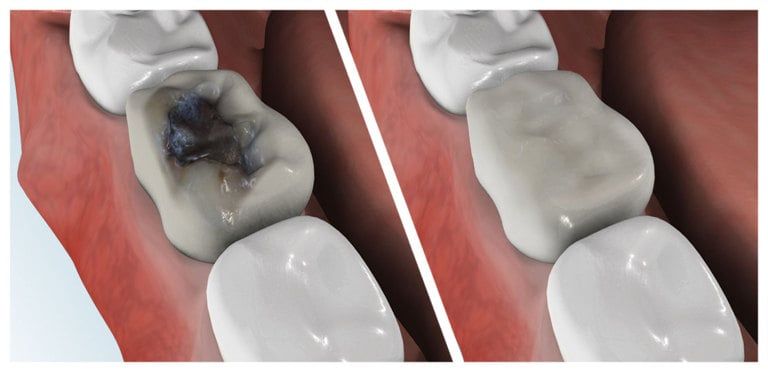

A filling is a way to restore a damaged tooth back to its normal function and shape. When you get a filling, the dentist will remove the decayed material from the tooth, clean the affected area, and then fill the area with a material designed for fillings. There are many types of filling material available, ranging from gold to porcelain.

Composite fillings are today's modern filling choice. They are made to match your tooth's natural color to make them virtually invisible to notice and are placed onto the tooth by bonding the filling material to the tooth so they do not have the unlikely chance of falling off. Many patients choose to replace their old silver and gold fillings with composite fillings.